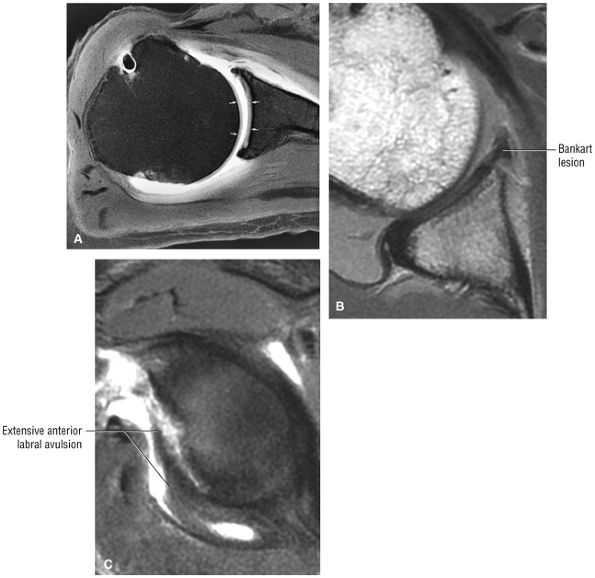

FIGURE 8.4 ● (A) Axial FS PD FSE image shows intact and congruous humeral head and glenoid articular cartilage surfaces (arrows), separate from the high-signal-intensity intra-articular contrast. (B) PD FSE contrast without FS is shown in an axial image of a Bankart lesion. Chondral surfaces are not as well demonstrated. (C) Excellent contrast is shown between the avulsed anterior labrum and the anterior glenoid rim on the corresponding sagittal FS PD FSE image.